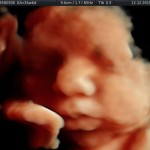

Modalidad de imagen ecográfica que permite evaluar, medir y capturar estructuras fetales superficiales e internas en 3 dimensiones (3D) y también en movimiento y en tiempo real (4D) con programas de realismo aumentado (HD LIVE) e imágenes tomografías fetales (TUI) mejorando significativamente la precisión en las mediciones fetales y la documentaciones de estructuras anatómicas.

Esta tecnología se puede utilizar desde la 6ta a la 40ma semana de embarazo.